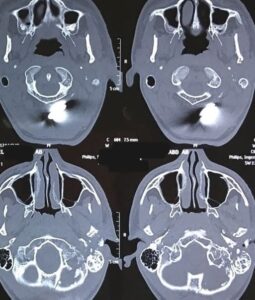

كان المستشفى الرئيسي قد استقبل شاب يبلغ من العمر ١٦ عاما، في حالة غيبوبة، نتيجة استقرار رصاصة خلف أذنه اليسرى، مما تسبب في قطع تام بالعصب الوجهي السابع، وبعد قضاء أسبوعين في العناية المركزة، خضع المريض لعملية جراحية دقيقة لاستكشاف العصب السابع، حيث قام الأستاذ الدكتور محمد محمود رشدي، بتحديد مكان القطع في العصب، ونظرا لتلف جزء كبير من العصب، قام الأستاذ الدكتور محمد مدثر أبو شنيف، بإجراء عملية جراحية استغرقت ٦ ساعات، لأخذ وصلة عصبية من أحد الأعصاب الحسية الجلدية وإعادة توصيل العصب السابع بالعصب المسئول عن حركة اللسان، دون أي تأثير على حركة اللسان.